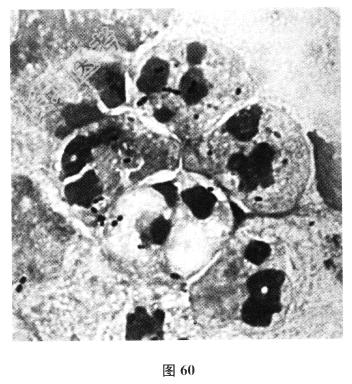

- 多项选择题2.痰涂片结果如图60所示,如何报告结果()

A、检出革兰阳性菌

B、检出革兰阳性球菌,成对排列

C、检出球菌

D、检出葡萄球菌

E、检出肺炎链球菌

F、检出卡他莫拉菌